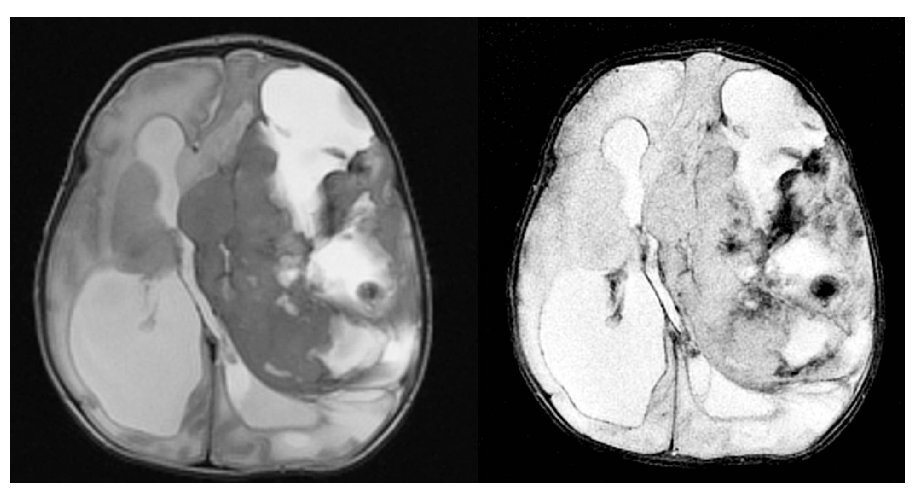

Gestante en el séptimo mes del embarazo. En ecografía de control se detecta hidrocefalia.

Fig. 1.